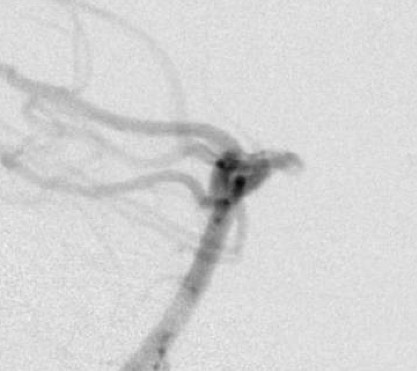

最终脑血管造影示所有分支血流通畅,动脉瘤无显影。